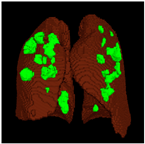

Based on the results of the evaluation metrics for each architecture in Table 6, similar to the lung segmentation case, in the lung and infection segmentation case, 3D UNet is better than the other six methods. Compared with the 3D VGGUNet architecture with transfer learning, which achieved the second-best result on average, 3D UNet improved by 8.18%, 7.39%, 0.38% and 0.38% in IoU score, Dice score, accuracy, and F1-score, respectively. Although 3D Unet has the best evaluation of metrics compared to other architectures, 3D UNet has the longest maximum learning iteration process of 1510, in contrast to other architectures, which are modifications of 3D UNet, and which have an average maximum learning iteration of 233. Of the seven models that have been tried, 3D DenseUNet without transfer learning obtained first place as the architecture with the fastest learning time, specifically ±4602 s. The 3D UNet architecture stays in the second to last position with a learning process time of ±12320 s, and in the position of the architecture that has the longest training process is the 3D VGGUNet with transfer learning, reaching ±8702 s. The comparison of loss training and testing on the 3D UNet learning process for the lung and infection segmentation is shown in Figure 5. Furthermore, in Table 8, the comparison of ground truth and the prediction results of the 3D UNet model in 2D (slice) and 3D projections in this multi-class segmentation case can be seen.

Table 8. Comparison between ground truth and prediction results of lung and infection segmentation with 3D UNet architecture.

Original CT-ScanGround TruthPrediction

3D ProjectionHealthcare 11 00213 i036Healthcare 11 00213 i037Healthcare 11 00213 i038

SliceHealthcare 11 00213 i039Healthcare 11 00213 i040Healthcare 11 00213 i041